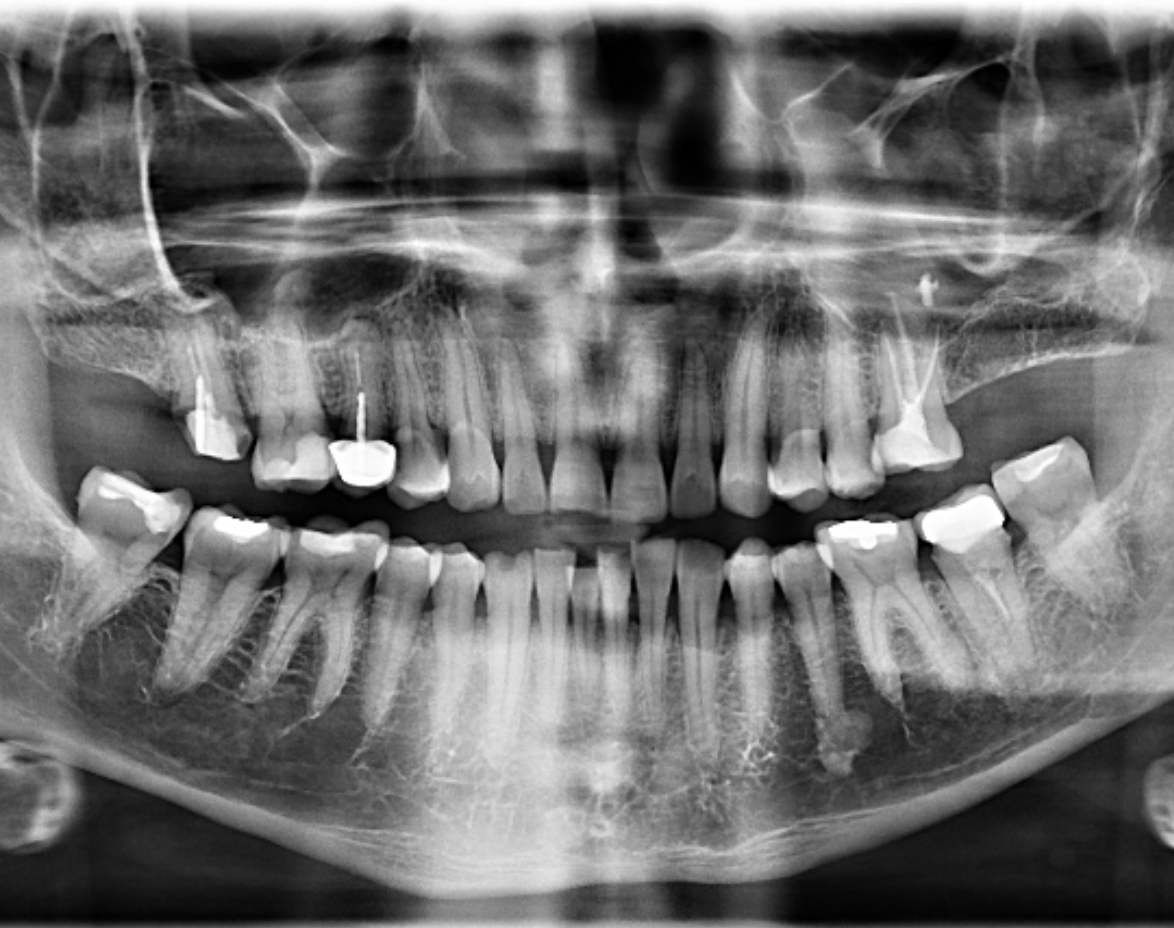

Paciente masculino de 45 años acude para una evaluación general. A la evaluación de la radiografía panorámica (Figura 1) se observa engrosamiento de la mucosa de seno maxilar izquierdo además de una imagen radiopaca proyectada en seno maxilar izquierdo; así mismo en pieza 26 se observa restauración coronaria, sellado cameral y obturación de conductos. A la evaluación de la tomografía volumétrica (cone beam) bimaxilar en los cortes axiales (Figura 2), coronales (Figura 3) y transaxiales (Figura 4) se observa que la pieza 26 presenta obturación de conductos además del engrosamiento de seno maxilar izquierdo e imagen hiperdensa de alta densidad, de

forma irregular, localizada en la mucosa de seno maxilar izquierdo.